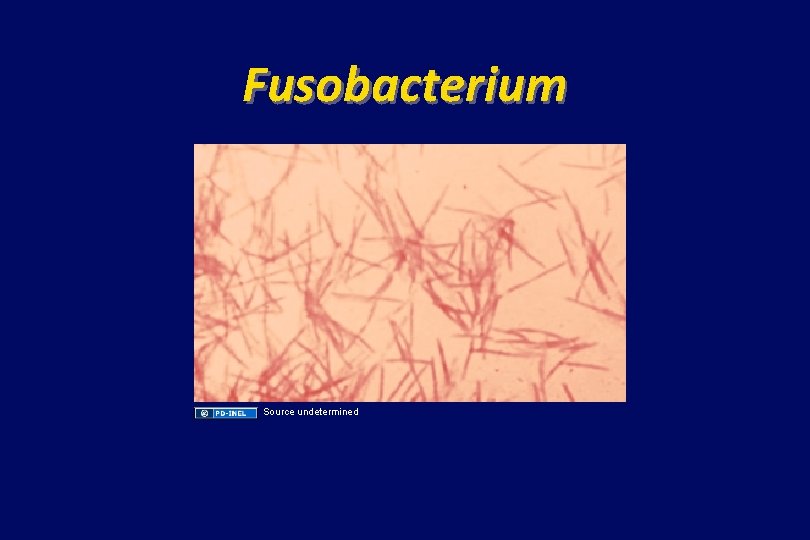

Fusobacterium Source undetermined

Additional Source Information for more information see: http: //open. umich. edu/wiki/Citation. Policy Slide 10: Yu J, Fulcher AS, Turner MA, Halvorsen RA. Helical CT Evaluation of Acute Right Lower Quadrant Pain: Part I, Common Mimics of Appendicitis Am J Roentgenol. 2005; 184(4): 1136 -1142. Resource: medscape. com Slide 12: Source undetermined Slide 13: CDC: Public Health Image Library/Dr. V. R. Dowell, Jr. , 1972, http: //phil. cdc. gov/phil_images/20030203/6/PHIL_3084_lores. jpg Slide 31: Abhijit Datir, Lung Abscess, Radiopaeidia. org, http: //radiopaedia. org/articles/lung_abscess Slide 32: Source undetermined Slide 33: Source undetermined Slide 39 & 40: Lin D, Suwantarat N, Young RS. Lemierre’s Syndrome mimicking leptospirosis. Hawaii Med J. 2010; 69(7): 161 -63. http: //www. hawaiimedicaljournal. org/69. 07. 161. htm Slide 41: Source undetermined